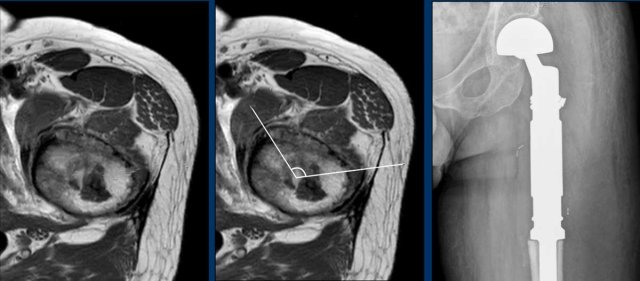

Images

MRI cor T1W-image shows an eccentric,

slightly expansile lesion in the caput and collum of the right femur.

It is difficult to appreciate whether

the medial cortex is only thinned or destructed.

Therefore an unenhanced CT was done

in addition.

Unenhanced CT demonstrates a lytic

lesion containing chondroid matrix calcifications.

There is cortical scalloping

medially, but no cortical destruction.

Curettage was performed to exclude a clear cell chondrosarcoma. This is a rare subtype of chondrosarcoma which occurs in the epiphysis of long bones in young adults.

Pathology diagnosis: ACT.

There is an osteolytic, expansile

lesion in the right proximal femur diaphysis.

Adjacent subtle cortical

thickening is present without periosteal reaction.

No frank chondroid matrix is

appreciated on this radiograph.

Conclusion

The differential diagnosis would include chondrosarcoma,

fibrous dysplasia, lymphoma, metastasis and plasmacytoma.

An unenhanced CT could help in

detection of subtle chondroid matrix calcifications in this case. However, we

went straight for MRI.

Continue with the MRI...

First look at the images.

Then continue reading.

T1W-image shows marrow replacement.

T2W-image shows periosteal reaction

and perilesional bone marrow edema.

The tumor itself is hyperintense and

nodular.

T1W FS post Gd-image shows rings-and-arcs

enhancement pattern.

All these findings are in keeping

with a chondroid tumor, and very suspicious of a chondrosarcoma of grade II or

higher.

In our tertiary referral center for

bone sarcomas we perform no biopsy in these chondroid tumors, as this may cause

sampling error due to heterogeneity within the tumor.

You may erroneously biopsy the

friendlier part of the tumor and underestimate the grade.

Chondroid tumors are known for their seeding along the biopsy tract.

Continue with the postoperative X-rays.....

Treatment consisted of en bloc resection of the proximal femur and reconstruction with an endoprosthesis.

Pathology confirmed a chondrosarcoma grade II.